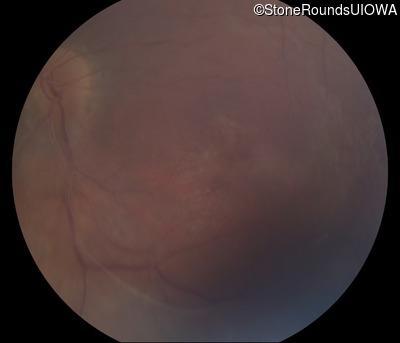

Visit at age: 45 years

Fundus Photography - Right - 20/50 +2

Exemplar

Fundus Photography - Left - 20/160